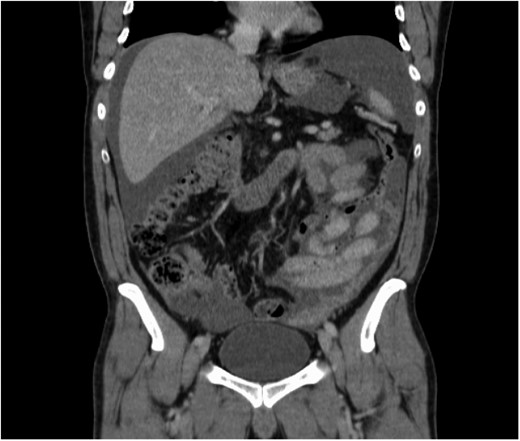

On initial examination, he was pale looking, afebrile and vitally stable; the abdomen was soft but distended. His initial blood investigations revealed microcytic hypochromic anaemia with haemoglobin of 9.2 mg/dl, low serum iron, transferrin, and ferritin, and high CRP (187 mg/l). Further workup was started with gastroscopy and colonoscopy, which were normal, followed by CT-TAP that showed multiple mesenteric implants with omental caking and gross ascites. No primary tumour localization was identified (Fig. 1a–d).

(a) Pelvic ascites. (b) Axial section showing omental caking. (c) Axial section showing omental caking. (d) Sagittal section showing peritoneal nodularity and ascites.